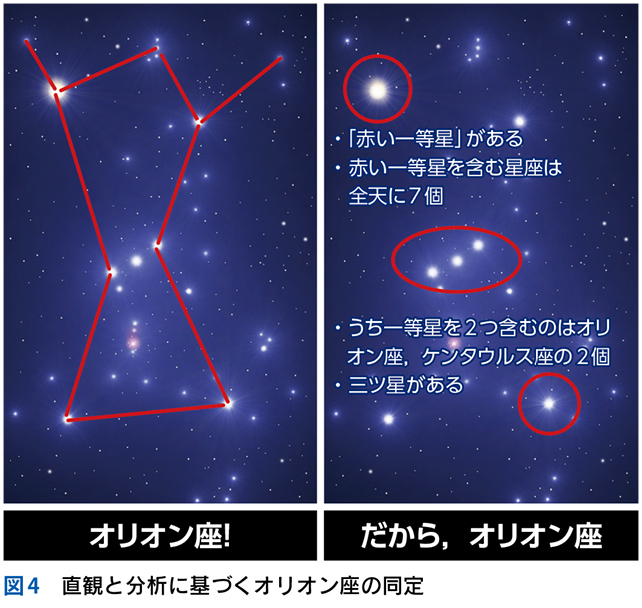

▶ 個々のプロブレムのyieldを,星座を構成する星にたとえれば,high yieldなプロブレムとは一等星である(図4)。その星があるというだけで,可能性のある星座の数が絞られる。low yieldなプロブレムは,星座を構成する二等星以下の星だ。その星(だけ)に注目しても,構成可能な星座の数が多すぎてあまり役には立たない(ただし,二等星以下の星も後述する「順位づけ」では活躍するし,オリオン座の三ツ星のように,二等星以下の星の「組み合わせ」が有力な1つの問題;症候群を形成し,一等星相当になることもある)。

5 ノイズと多元論

▶ 「ノイズ」は,筆者的には臨床推論においてきわめて重要な概念であるため,第4章で詳述するが,フレーミングに関わるのでここで簡単に紹介しよう。ここでは「ノイズ」を,「患者の持つ情報のうち診断と直接的には関連しないもの」を指す語として使用する。対義語(診断と関連する情報)は「シグナル」である。星座のたとえで言えば「シグナル」は星座を構成する星,「ノイズ」は星座を構成しないが近傍にある「くず星」を指す(図4)。